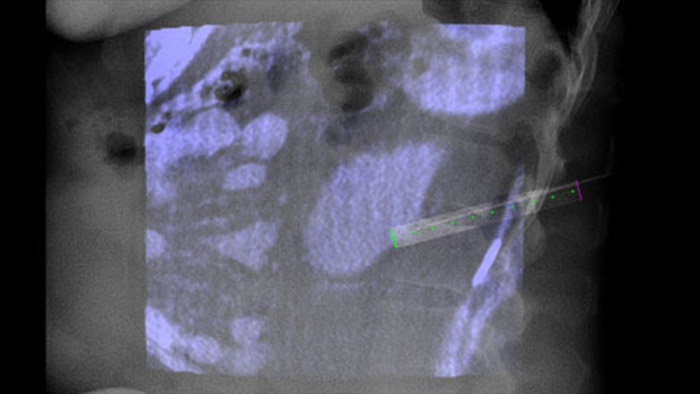

O XperGuide fornece uma orientação por imagem ao vivo altamente precisa de cada agulha para um posicionamento direcionado sobrepondo trajetórias pré-planejadas ao diagnóstico por imagem fluoroscópico.3

O recurso Dual View permite a sobreposição de uma imagem 3D pré-procedimento (TC/RM/PET-TC) a uma CBCT Dupla 3D intraprocedimento para uma melhor visualização das lesões e acesso a dados cruciais para o planejamento da agulha.

Navegar com precisão até a lesão em questão com baixa dose e sem reposicionamento da agulha aumenta a chance de sucesso e reduz o risco de complicações de suas biópsias ou ablações. A confirmação do desfecho do tratamento de ablação pode ser realizada com diagnósticos por imagem 3D enquanto o paciente ainda está na mesa.